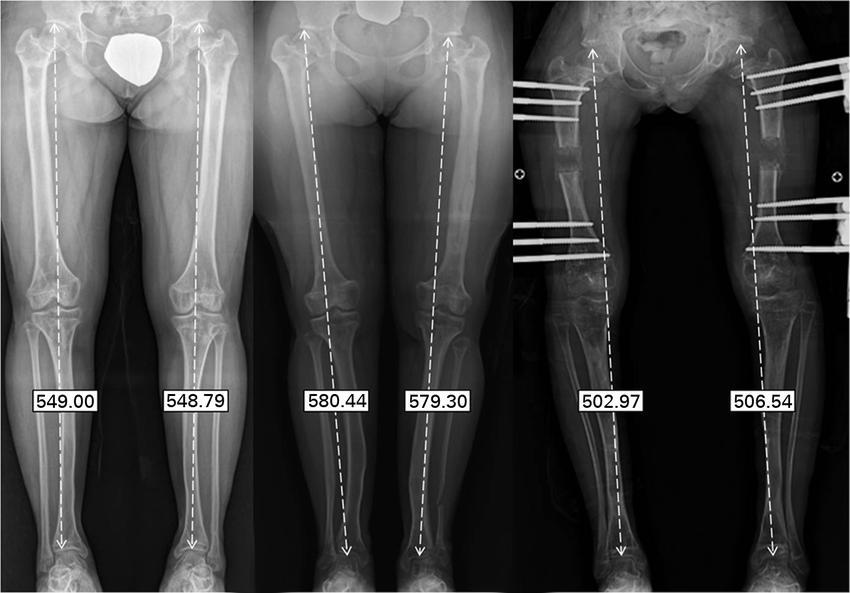

أشعة قياس الزوايا والأطوال المعروفة بأسم scanogram هى نوع من الأشعات مشابه بدرجة كبيرة للاشعة العادية يتم فيه تصوير الطرف السفلي كاملاً بدءًا من الحوض و حتى القدم على صورة واحدة.

بعدها يتم استخدام الكمبيوتر لتحديد العديد من القياسات على الأشعة بدقة كبيرة، و تستخدم هذه الأشعة بصورة كبيرة لقياس أطوال العظام و لا سيما قبل جراحات تطويل العظام و لقياس فرق الطول بين الساقين.

كما ان هذه الأشعة مفيدة لقياس مقدار وزاوية و موضع تقوس الساقين و لا سيما قبل جراحات استعدال تقوس الساقين, حيث يتم مد خط من منتصف مفصل الفخذ الى منتصف مفصل الكاحل (الخط الاحمر فى الصورة).

فى الأشخاص الطبيعيين يجب أم يمر هذا الخط قرب منتصف مفصل الركبة، و لكن فى حالات تقوس الساقين يبتعد هذا الخط عن منتصف الركبة كلما زادت زاوية التقوس.

يتوجب على فني الاشعة ان يتأكد من أخذ لقطة الاشعة دون وجود التفاف أو انثناء في الركبة أو الساق أو الفخذ لضمان دقة قياس الزوايا. كما يجب ان تكون عظمة الصابونة مواجهة للأمام مباشرة.